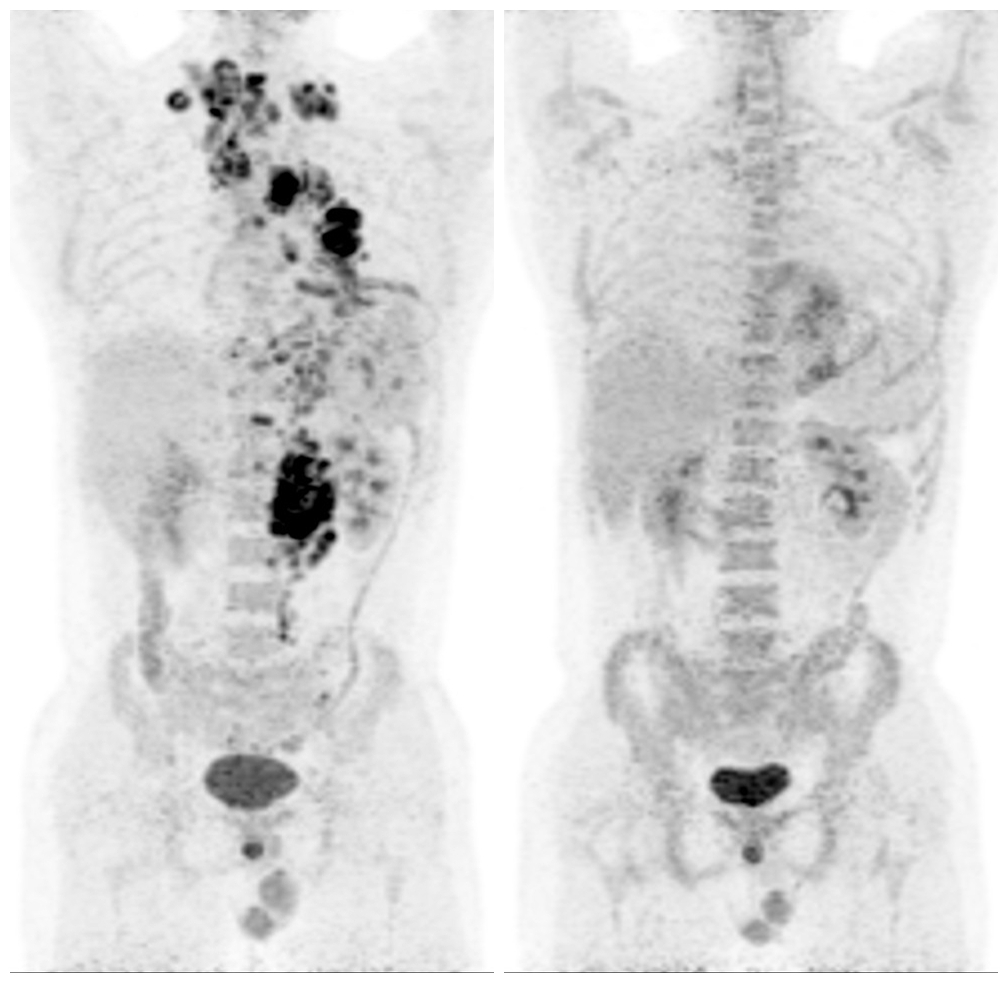

治疗前MIP图像 | 化疗后MIP图像 | 治疗前PET-CT图像 | 治疗后PET-CT图像 |

病例四 疗效评价 男,27岁。弥漫性大B细胞淋巴瘤化疗前、化疗后半年后PET-CT检查对比,显示病灶已消退,代谢水平已趋于正常,Deauville评分1分。